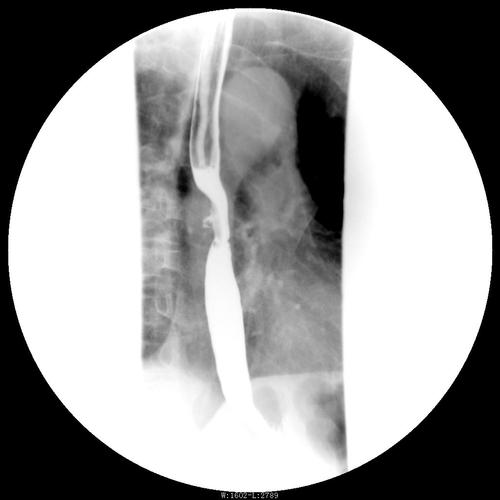

上消化道造影检查技术及常见病变的x线诊断

食管造影